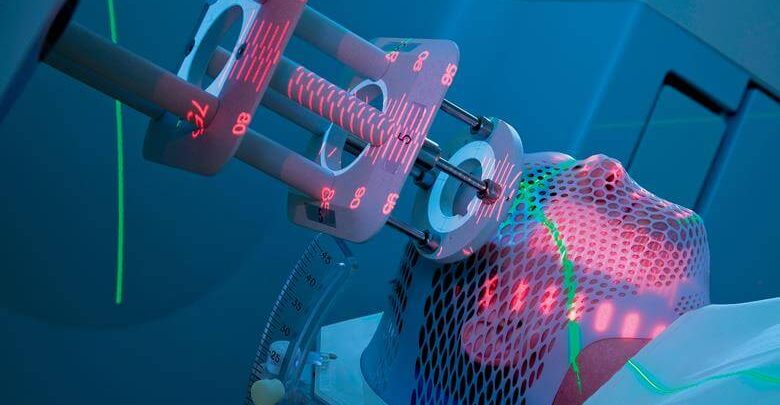

Görüntü rehberliğinde radyoterapi; kanserli bölgenin 2 ya da 3 boyutlu radyolojik görüntüleme yöntemleriyle tespit edilmesi ve yüksek dozdaki radyasyonun hedef bölgeye gönderilmesi işlemidir. Bu görüntüleme özel cihazlarla hem tedavi öncesinde hem de tedavi sırasında yapılır. Hedefin şaşmamasına son derece dikkat edilir. Çünkü uygulanan radyasyon kanserli hücrelere seçici değildir. Uygulandığı bölgedeki normal ya da kanserli her hücreyi harap eder. Yine de kanserli hücreler normal hücrelere göre radyasyona karşı daha dayanıksızdır.

Radyoterapi uygulaması, bu iş için özel olarak tasarlanan cihazlarla donatılmış özel bir odada yapılmaktadır. Kanser hastalarının %80’inde radyoterapi vücudun dışından yapılır. Dışarıdan yapılan bu uygulamaya external radyoterapi denilir. Uygulamada sırasıyla şu adımlar izlenir:

- Işınlanacak bölgenin görüntüsü ortaya çıkartılır. Bu görüntüleme 2 boyutlu ya da 3 boyutlu olabilir. Bu hem cihazın özelliklerine hem de incelenecek vücut bölgesinin derinliğine göre değişir.

- Yer iyice tespit edildikten sonra radyasyonun dozu ayarlanır ve hedef bölgeye aktif bir şekilde gönderilir. Genellikle bu aktif ışıma 2 ya da 3 dakikayı geçmez. (Hastanın genel durumu bu sürede belirleyicidir.) Yaklaşık 15-20 dakika içerisinde radyoterapi bitmiş olur ve bu sürenin sonunda kişi personel yardımı ile dışarıya çıkartılır.